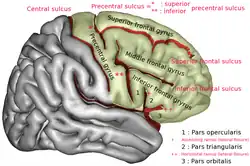

Superior frontal gyrus of the human brain | |

In neuroanatomy, the superior frontal gyrus (SFG, also marginal gyrus) is a gyrus – a ridge on the brain's cerebral cortex – which makes up about one third of the frontal lobe. It is bounded laterally by the superior frontal sulcus.[1]

The superior frontal gyrus is one of the frontal gyri.

Position of superior frontal gyrus (shown in red)